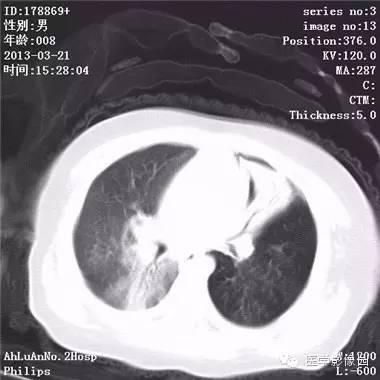

患儿男,8个月,呛咳,发热一周。实验室检查白细胞及中性粒细胞增高。

两肺肺纹理增多、增粗,右肺可见斑片状、片絮状模糊影,边界欠清;左肺上叶见楔形高密度影,内可见支气管征,尖端指向肺门;左肺下叶肺野透亮度增强;另见左肺主支气管内可见块状软组织密度影。

支气管异物(花生米)伴两肺炎症(追问病史,患儿奶奶层于一周前喂食患儿花生米,当时疑似“呛进去”,后来见好了也就没留意)。